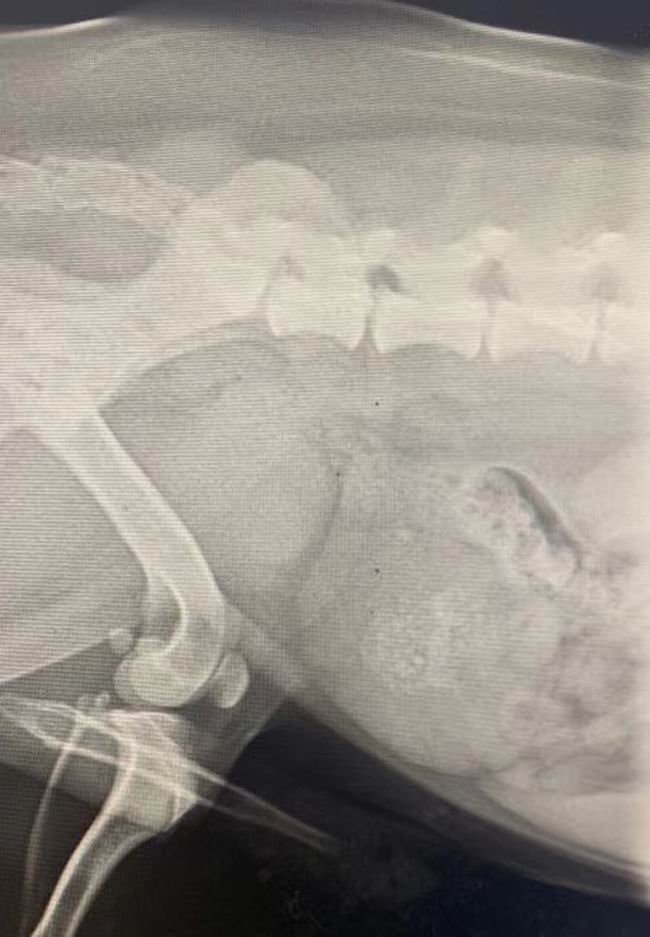

膀胱結(jié)石手術(shù)一例

膀胱結(jié)石手術(shù)一例:柯基犬,三胖,3歲多,近期反復(fù)出現(xiàn)尿血現(xiàn)象,影像學(xué)確診為膀胱結(jié)石,術(shù)前檢查[表情]呼吸麻醉[表情]住院護(hù)理中。